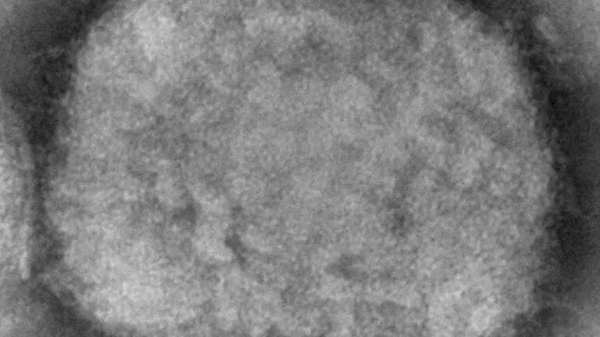

Maymun Çiçeği Virüsü nedir?

Maymun çiçeği virüsü, insanların genellikle batı ve orta Afrika'nın tropik bölgelerinde kaptığı nadir bir viral enfeksiyon. Genellikle virüsü barındırdığı bilinen sincap gibi hayvanlarla doğrudan temas yoluyla yayılıyor. Bununla birlikte, enfekte bir kişiyle çok yakın temas yoluyla da bulaşabiliyor. ilk olarak 1958'de araştırma için tutulan maymunlarda çiçek benzeri bir hastalık salgını meydana geldiğinde keşfedildi. İnsanda ilk kez 1970 yılında Demokratik Kongo Cumhuriyeti'nde görüldü. ve enfeksiyon o zamandan beri bir dizi Orta ve Batı Afrika ülkesinde rapor edildi. Afrika dışında sadece bir avuç vaka bildirildi ve bunlar normalde kıtayla seyahat bağlantıları olan insanlarla sınırlı.